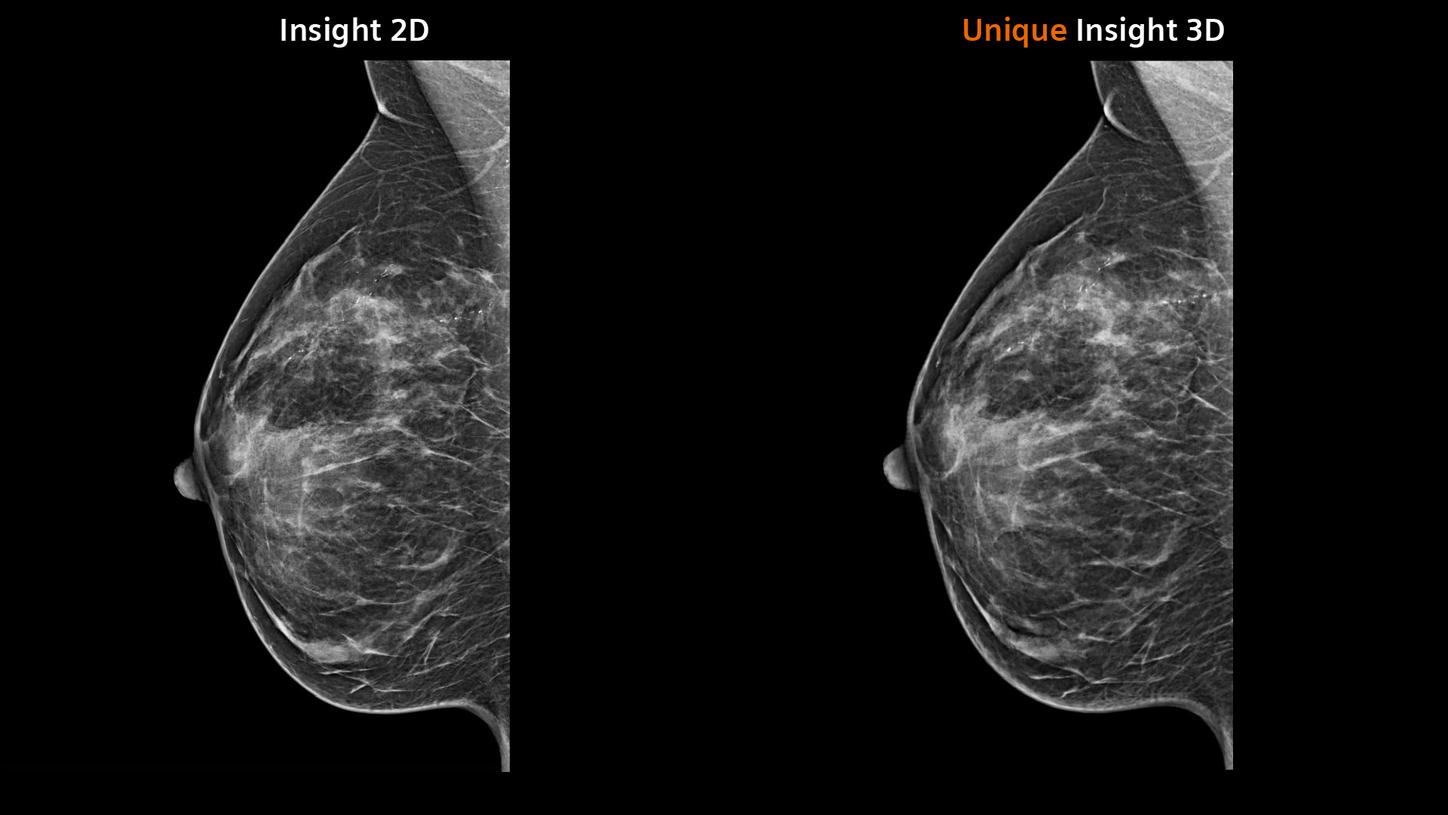

Synthetic imaging

Synthesized 2D mammographic imaging (Insight 2D) and unique, rotating synthesized

3D mammographic imaging (Insight 3D)